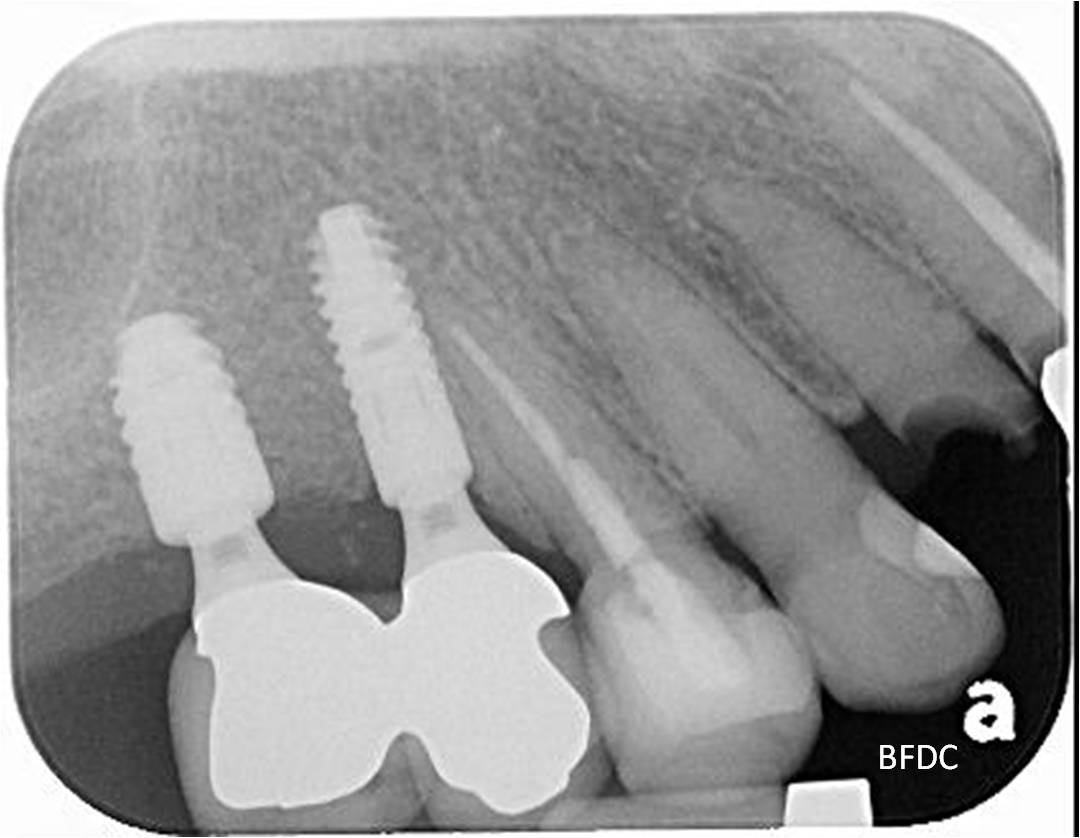

術後X光

透過適當的植牙手術與膺復處置,患者可以恢復正常的咀嚼與美觀功能,在後牙區如果採螺絲固定型假牙,則回診時,醫生只要將螺絲鬆開清潔假牙,對於後續後續清潔與維護有莫大的幫助。